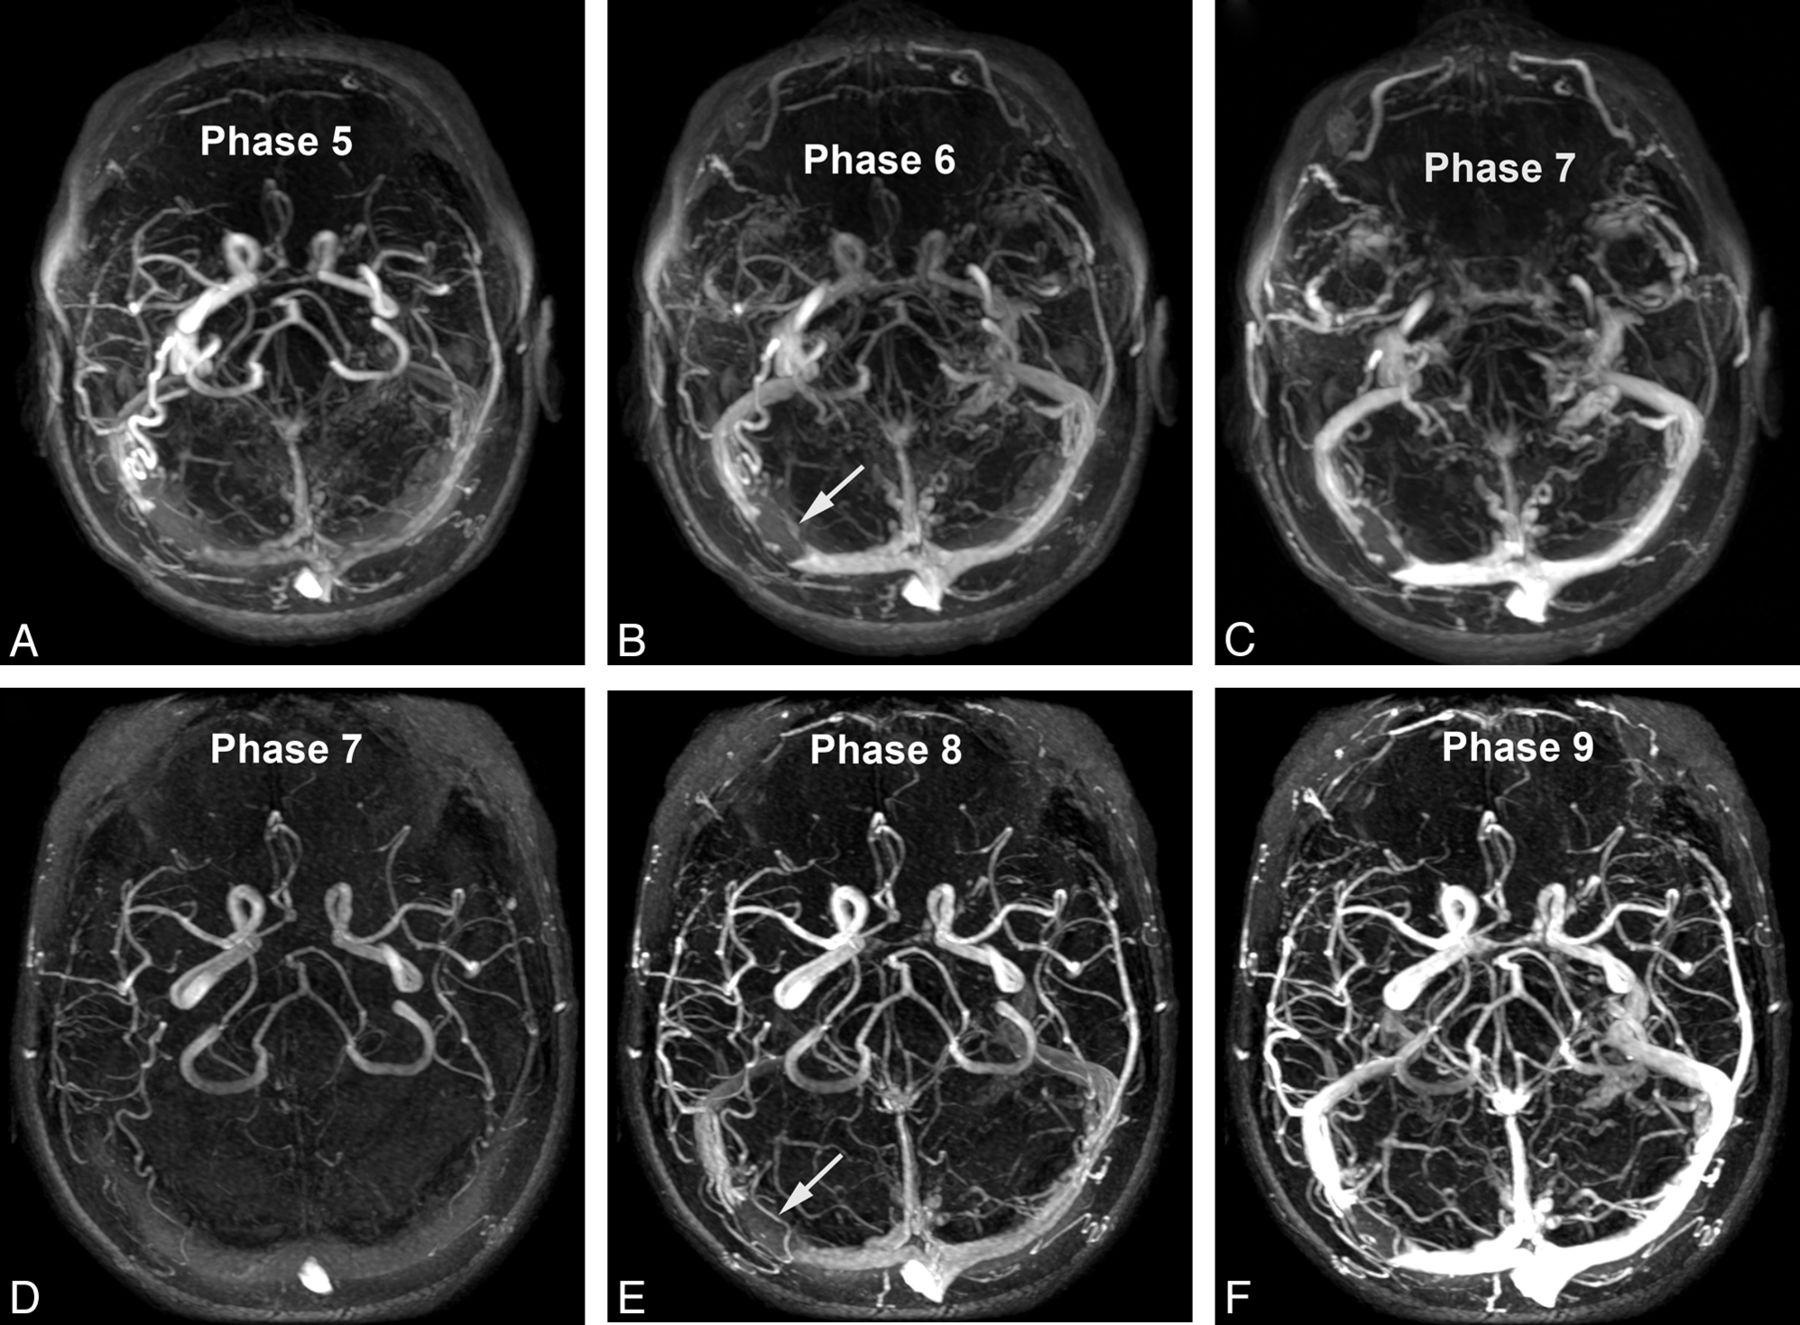

Patient (68-year-old woman) undergoing successive TR-MRA spaced approximately 1 year apart, for evaluation of angiographically documented indirect dural arteriovenous fistula (arrow). Images in A–C were obtained with injection of SCA; images in D–F were obtained with BPA. Early arterial (A, D), late arterial (B, E), and venous (C, F) axial MIP phases are presented as indicated. Qualitatively superior time-resolved angiography was scored for all temporal phases and arterial segments, with consideration to diagnostic confidence and vessel-background contrast. Note the generally delayed arrival/temporal phases with the slower administration rate of BPA.

Whereas significant differences in quality were not identified between the agents for characterization of the superficial venous segments, venography of the deep system demonstrated significant superiority of BPA over SCA on subtracted and unsubtracted volumes (unsubtracted 2.92 ± 0.27 versus 2.74 ± 0.44, P = .016; subtracted 2.8 ± 0.4 versus 2.6 ± 0.53, P = .037, respectively).